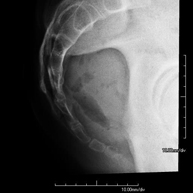

Procedimiento que permite, mediante el uso de rayos X, y tras inyectar un contraste en el interior de la articulación, detectar lesiones de determinadas articulaciones (cartílago, hueso, tendones, etc.) según la distribución del contraste. - RX Pelvis

Procedimiento mediante el cual, utilizando rayos X, se obtienen imágenes de la pelvis para su estudio, especialmente de los huesos pélvicos. - RX Edad ósea

Estudio que, utilizando los rayos X, permite obtener una imagen de los huesos de la cadera y descartar luxaciones. - RX Seriada ósea

Estudio que, utilizando los rayos X, permite obtener una imagen de los huesos de la cadera y descartar luxaciones. - Cistografía